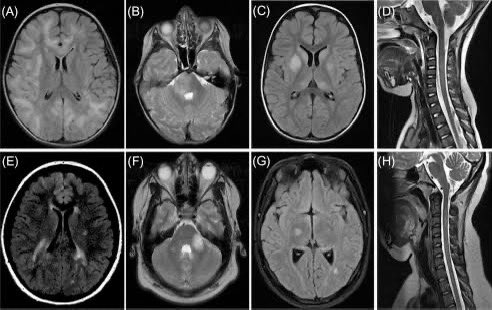

A new research underscores how much more we have to learn about what SAR-CoV-2 virus can do to our children, particularly to their brains. The study collected brain scan data from nearly 2 years’ worth of scientific literature to try to summarize what we know so far. 1/ Image

The systematic review & meta analysis of 96 studies finds that a substantial proportion of pediatric COVID-19 patients with neurological symptoms exhibit abnormal neuroimaging findings, with 43.74% of children in the included studies demonstrating such abnormalities. 2/ Image

The researchers identified different neurological signs in the children whose brains were scanned. They include neurovascular findings (8.22%), ADEM-like lesions (7.69%), encephalitic pattern (13.95%), myelitis (4.60%), transient splenial lesions (16.26%) & other 3/ Image